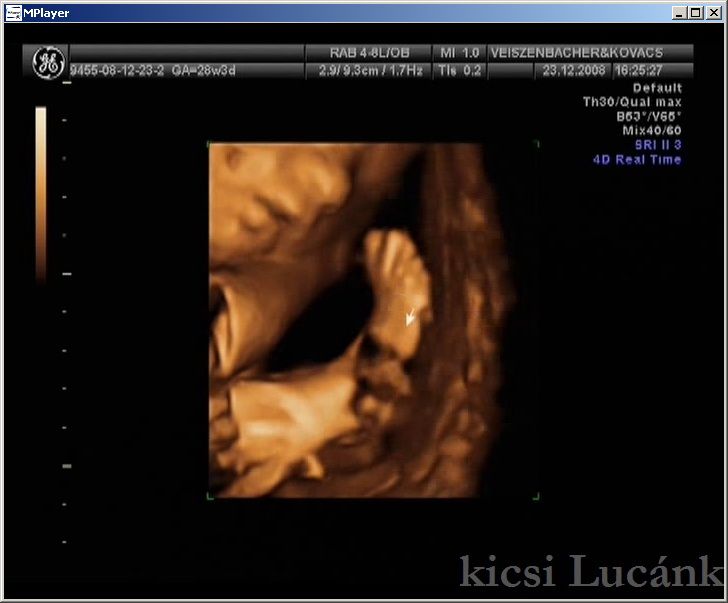

kicsi Lucánk - 2008.12.23 (10 of 13)

luca10